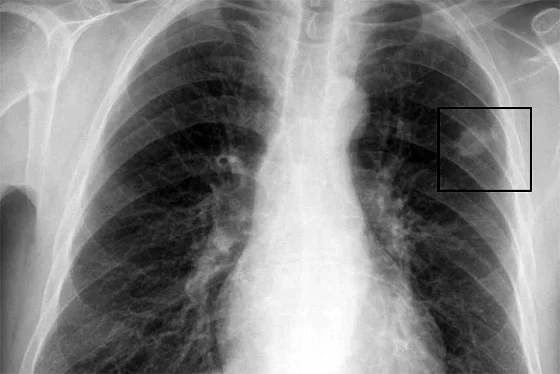

Jak stwierdził dyrektor Centrum, Aleksander Barinow-Wojewódzki, jest szansa, że po zarejestrowaniu leku, pierwsza partia szczepionek trafi do Wielkopolski. Podkreślił, że zaletą nowej szczepionki jest fakt, że może być stosowana wówczas, gdy wyczerpane są wszystkie znane dotychczas możliwości lecznicze. - Raka płuca można leczyć radioterapią, chemioterapią i przez leczenie chirurgiczne. Wskaźnik pięcioletniego przeżycia w niedrobnokomórkowym raku płuca wynosi ok. 10 - 14 proc. Przy wczesnym wykryciu i zoperowaniu raka przeżycie zwiększa się do 50-60 proc. Inną, nową metodą jest użycie szczepionki prof. Fakhraia. Ona zwiększa ten wskaźnik do ok. 40-50 proc. - powiedział.